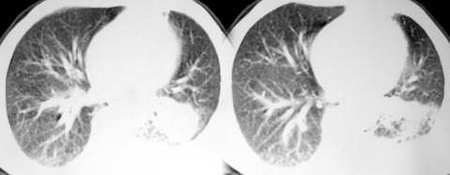

以下是引用sdqzwyx在2005-11-7 19:59:00的发言:[br]双肺弥漫大小不等的粟粒状结节影;肺纹理走行失去自然,粗细不均,边缘不规则,小叶间隔增厚;左上肺示不规则形致密影,从斑块边缘向周围伸出长短不一的致密索条影,临近的血管、支气管和叶间胸膜等结构受牵拉移位;左下肺示不规则团块状影,其内示空洞,洞内壁尚光整,左侧胸腔积液。右肺下叶背段亦示部分病灶融合。双肺可见局限性肺气肿。[br]诊断:结合病史符合三期矽肺表现(少数矽肺纤维斑块内可以形成空洞,一般认为是斑块中央感染引起坏死所致)但尘肺病人易合并肺结核,诊断可为三期+tb。所以此病人应进一步检查是否合并结核。